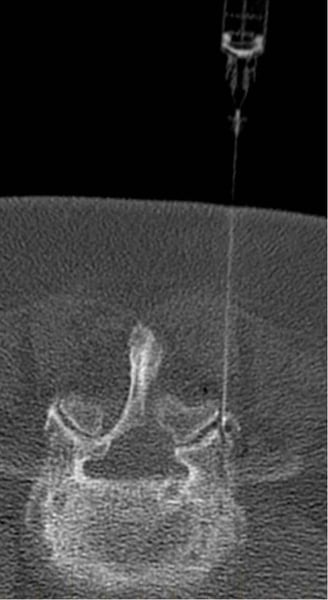

Vertebroplastias e Cifoplastias

A vertebroplastia e a cifoplastia são procedimentos minimamente invasivos utilizados para tratar fraturas por compressão na coluna vertebral. Na vertebroplastia, o médico injeta um cimento especial diretamente no corpo vertebral fraturado, fortalecendo-o e aliviando a dor. Já na cifoplastia, é inserido um balão na vértebra fraturada e, em seguida, o cimento é injetado no espaço criado, restabelecendo a altura vertebral e aliviando a dor. Ambos os procedimentos são realizados sob anestesia geral e levam cerca de 2 horas para serem concluídos. Após a cirurgia, os pacientes podem experimentar alívio imediato da dor e retomar gradualmente suas atividades normais. No entanto, é importante seguir as orientações médicas para garantir uma recuperação adequada.